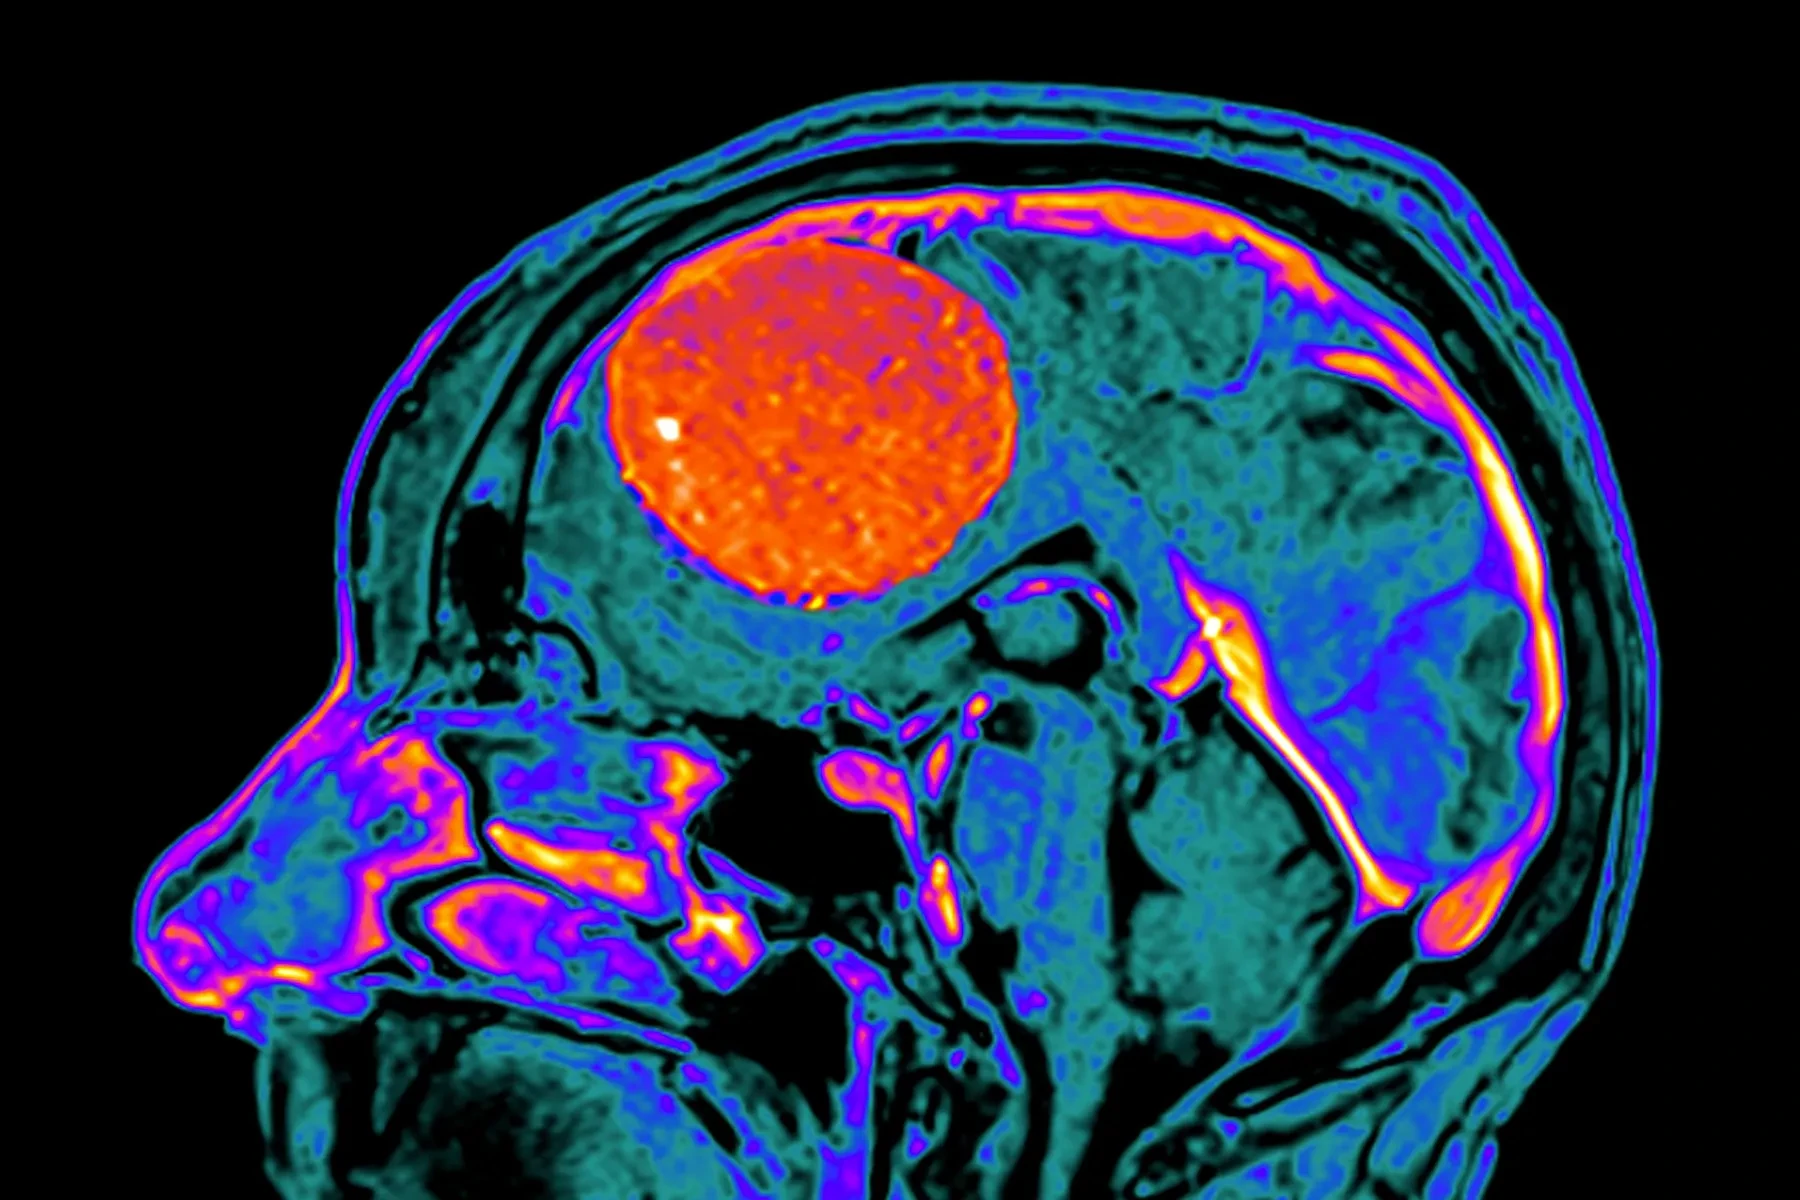

Il primo sintomo del meningioma, a cosa prestare la massima attenzione

Il meningioma è uno dei tumori cerebrali più comuni e, nonostante nella maggior parte dei casi sia ... ► tvzap.it